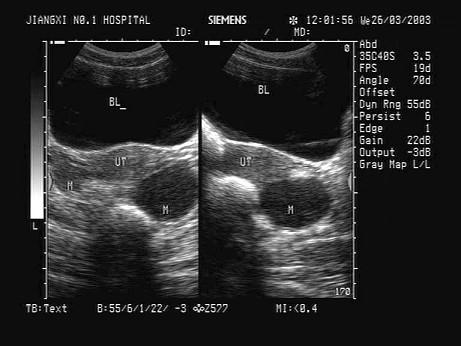

问题 某女患者子宫附件超声声像图如下,患者月经正常,有痛经及人流史,月经后7天检查。根据病史和图像,最可能的诊断为?(?)

选项 A.巧克力囊肿 B.滤泡囊肿 C.黄体囊肿 D.黄素囊肿 E.正常卵泡

答案 A